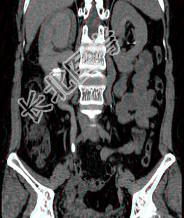

- 多项选择题患者女,44岁, 突发性胁腹部绞痛并向会阴部放射伴血尿一次。如图所示,以下说法正确的是 ( )

A、左肾输尿管未见异常

B、右输尿管内可见沿输尿管走行的高密度影

C、右侧肾盂肾盏扩张

D、右输尿管中上段扩张

E、右输尿管结石